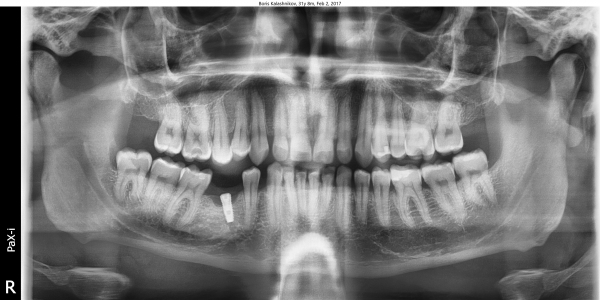

1,5 года назад поставил имплант в клинике "N". Спустя примерно год собрался его протезировать в другой клинике, так как переехал жить в другой город. Там мне сказали, что для данного места поставленный имплант очень маленький. Зуб не будет на нем держаться, так как вкручен он неверно, криво.